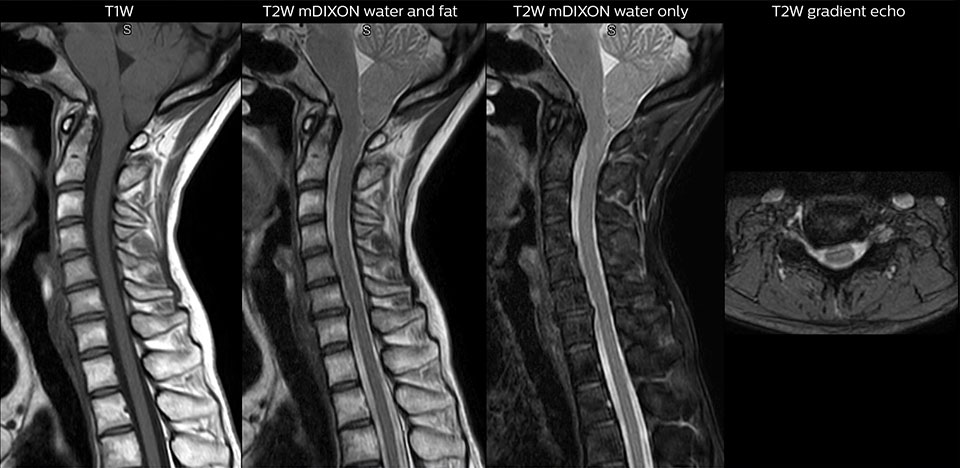

cervical spine mri in ed

Cervical spine routine exam

This patient presented with headache that was worse with neck flexion and we see a Chiari 1 malformation with low-lying cerebellar tonsils as well as some degenerative cervical thrombolytic change.